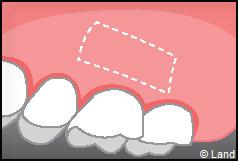

Les greffes de conjonctifs enfouis :

Destinées aux zones esthétiques, elles consistent à prélever la partie profonde du palais (site donneur).